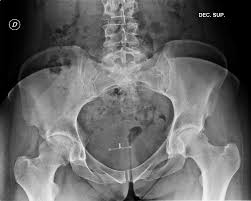

2) 영상검사와 보조 검사 🖼️

X선으로 관절 간격과 골극을 보고, MRI로 연골과 비구순, 힘줄 상태를 평가해요. 필요 시 초음파로 점액낭의 염증을 확인하고 주사 치료를 유도할 수 있어요. 염증성 질환이 의심되면 혈액검사도 병행해요.